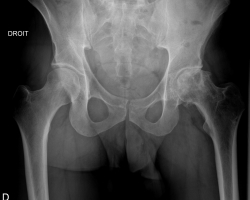

La coxarthrose, ou arthrose de la hanche, est une des arthroses les plus fréquente, juste après celle du genou. C’est aussi l’une des causes les plus fréquentes de douleur et d’incapacité fonctionnelle chez les sujets de 55 ans et plus. Sa prévalence augmente en effet avec l’age avec une légère prédominance féminine après 50 ans.